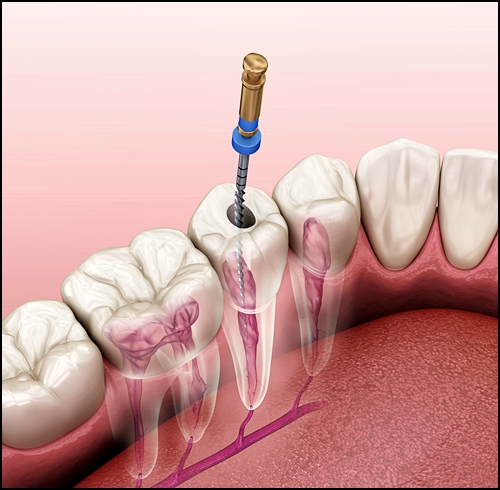

예를 들어, 신경치료 같은 경우 보험이 적용되기 때문에 병원마다 비용 차이는 크지 않습니다.(재료에 따라 달라질 수는 있습니다)

하지만 신경치료를 하는 의사의 '실력'은 차이가 있겠죠.

우리나라에서 신경치료와 같은 보험 치료는 병원에 큰 이익을 안겨주지 않기 때문에 이를 치료하는 의사가 적고, 결과적으로 치료에 질적인 차이가 생길 수밖에 없습니다.

크라운은 기본적으로 '신경치료'가 잘 되었을 때 오래 사용할 수 있습니다.

즉, 기초 공사를 잘 끝내야 치아 크라운 수명도 길어질 수가 있는 것인데요.

즉, 크라운 가격이 치료의 질을 보장하지 않는다면, 같은 재료를 같은 방식으로 사용한다고 해도 치과의사의 실력과 노하우에 따라 결과는 바뀔 수 있습니다.